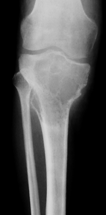

Kemiğin selim-agresif tümörü olarak kabul edilir. Genç erişkinde osteolitik karakterde kemik tümörüdür. Uzun kemiklerin ekleme yakın uç kısmından çıkabilir. Hastalar tümör bölgesinde devamlı ve giderek artan inatçı bir ağrı ve şişlik ile başvururlar.Sadece küretaj yapılan hastalarda yüksek lokal nüks yanında akciğer metastazı yapma potansiyeli olduğundan lokal agresif tümör olarak kabul edilir. Ama bu metastazlar ölümcül değildir.Diz eklemi en sık tutulan bölgedir. Diğer sık tutulan bölge el bileğidir. Kemik korteksini harap ederek yumuşak dokulara yayılım gösterebilir. Tanı için biyopsi şarttır. Brown tümörü ile ayırıcı tanısı yapılmalıdır. Tanı esnasında akciğer tomografisi çekilmelidir.

Tedavide genişletilmiş küretaj ve adjuvan ajanlarla kalan tümör hücreleri öldürülmeye çalışılır. Adjuvan ajan olarak; sıvı azot, alkol, fenol, argon koter, kriyoterapi, yüksek hızlı burr ve sementleme (kemik çimentosu) uygulanır. Eklemin tutulduğu vakalarda eklem feda edilir,protez veya artrodez uygulanabilir. Rezeksiyonun zor olduğu olgularda denosumab kullanılması önerilmektedir.Hastaların lokal nüks ihtimaline karşı 10 yıl süre ile takibi yapılmalıdır.